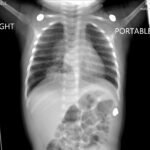

Infant tuberculosis (TB) is a rare but potentially deadly infection and difficult to diagnose, especially in infants who may present with non-specific symptoms. Here, we report a case of an United States-born term infant with community-acquired miliary TB and no confirmed TB exposure history. The patient initially presented with respiratory distress at seven weeks of life with chest radiograph showing a right lower lobe (RLL) infiltrate. After failing multiple courses of treatment for community-acquired pneumonia and developing growth faltering, the patient had imaging findings suggestive of TB infection with CNS involvement. The diagnosis of TB was confirmed by QuantiFERON and purified protein derivative (PPD). In infants who fail conventional treatment for bacterial pneumonia, the differential should be broadened to consider alternative etiologies. Additionally, brain imaging should be performed in cases of disseminated TB despite negative cerebrospinal fluid (CSF) studies since these patients are at high risk of central nervous system (CNS) involvement.